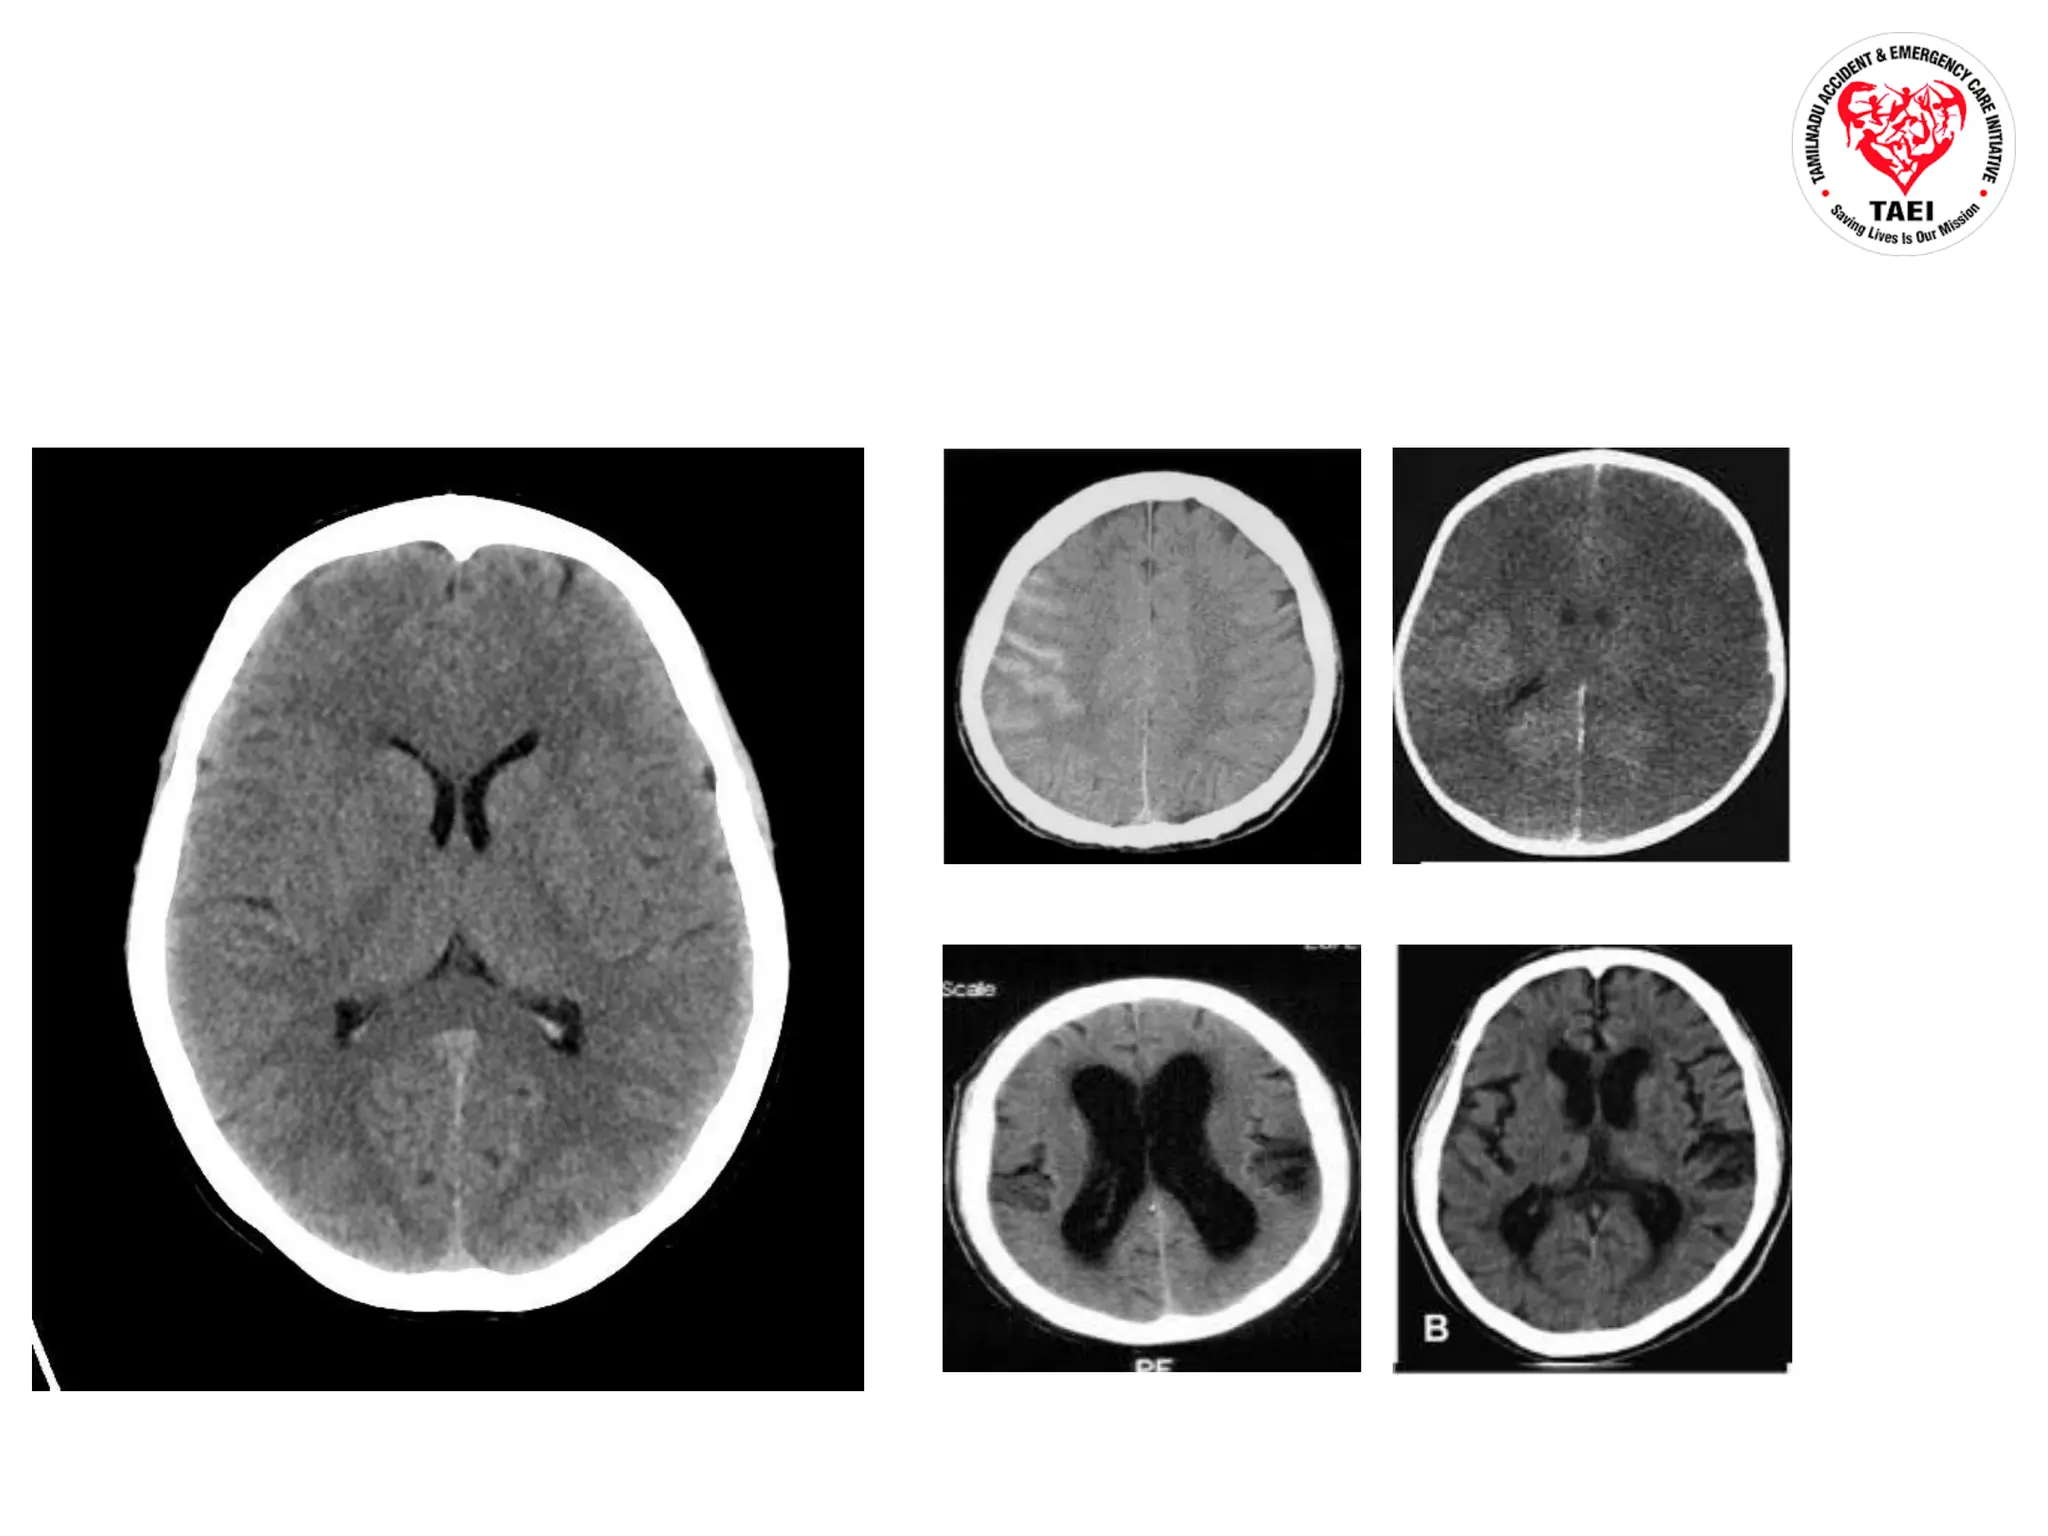

Psychiatry Traumatic Brain Injury Ppt Ppt Ppt Blast induced tbi results from exposure to blast overpressure (bop), which generates shock wave energy that transmits force throughout the skull and can impact brain tissue. Traumatic brain injury (tbi), causes substantial disability and mortality. it occurs when a sudden trauma damages the brain and disrupts normal brain function. Rapid acceleration or deceleration, direct compression, penetration and physical disruption of brain tissue, blast injuries, etc. what type of trauma will these patients typically present with? mvc, pedestrian impact, falls, and assault. Traumatic brain injury (tbi) is caused by an external force to the head that can lead to temporary or permanent impairment. it is a leading cause of death and disability, especially in young people. A traumatic brain injury (tbi), also known as an intracranial injury, is an injury to the brain caused by an external force. tbi can be classified based on severity ranging from mild traumatic brain injury (mtbi concussion) to severe traumatic brain injury. [5] tbi can also be characterized based on mechanism (closed or penetrating head injury) or other features (e.g., occurring in a specific. It describes the primary and secondary injury mechanisms of tbi, including diffuse axonal injury. imaging and diagnostic criteria for different types of brain injuries are outlined.

Psychiatry Traumatic Brain Injury Ppt Ppt Ppt Rapid acceleration or deceleration, direct compression, penetration and physical disruption of brain tissue, blast injuries, etc. what type of trauma will these patients typically present with? mvc, pedestrian impact, falls, and assault. Traumatic brain injury (tbi) is caused by an external force to the head that can lead to temporary or permanent impairment. it is a leading cause of death and disability, especially in young people. A traumatic brain injury (tbi), also known as an intracranial injury, is an injury to the brain caused by an external force. tbi can be classified based on severity ranging from mild traumatic brain injury (mtbi concussion) to severe traumatic brain injury. [5] tbi can also be characterized based on mechanism (closed or penetrating head injury) or other features (e.g., occurring in a specific. It describes the primary and secondary injury mechanisms of tbi, including diffuse axonal injury. imaging and diagnostic criteria for different types of brain injuries are outlined.